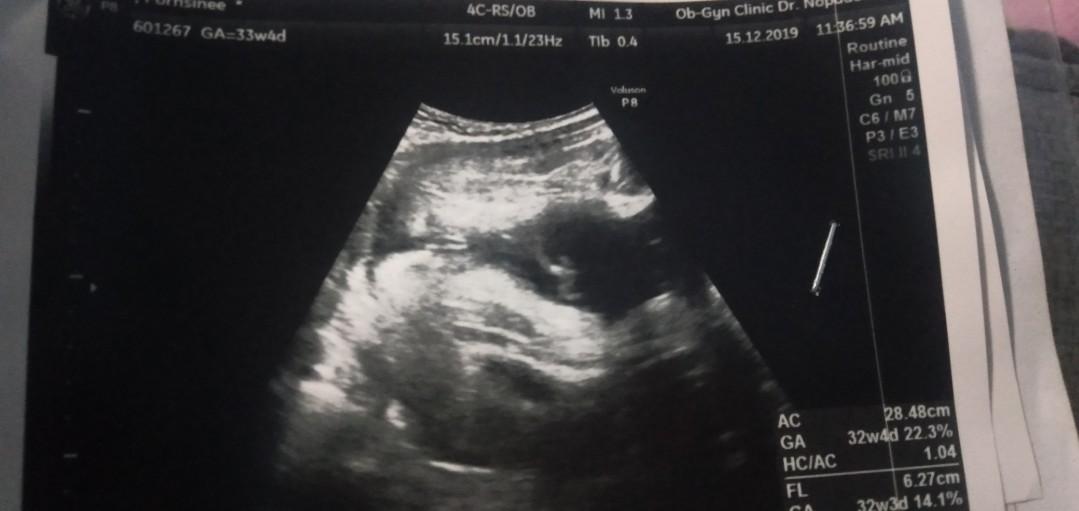

บ้านนี้มีกลีบค่ะ ชัดแจ๋ว😊😊

หมอบอกว่าหนูไม่มีจู๋คะ 😁😁😁